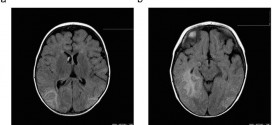

CÁNCER DE CABEZA

El cáncer de cabeza y cuello o de cerebro. El cáncer de cabeza es un ataque de pequeños tumores. Los médicos todavía no entienden las causas principales por las que aparecen los primeros tumores. Los tumores comienzan a crecer y diseminarse hasta que el cáncer se esparce por todo el cerebro. Cada vez que un tejido anormal o crecimiento celular …